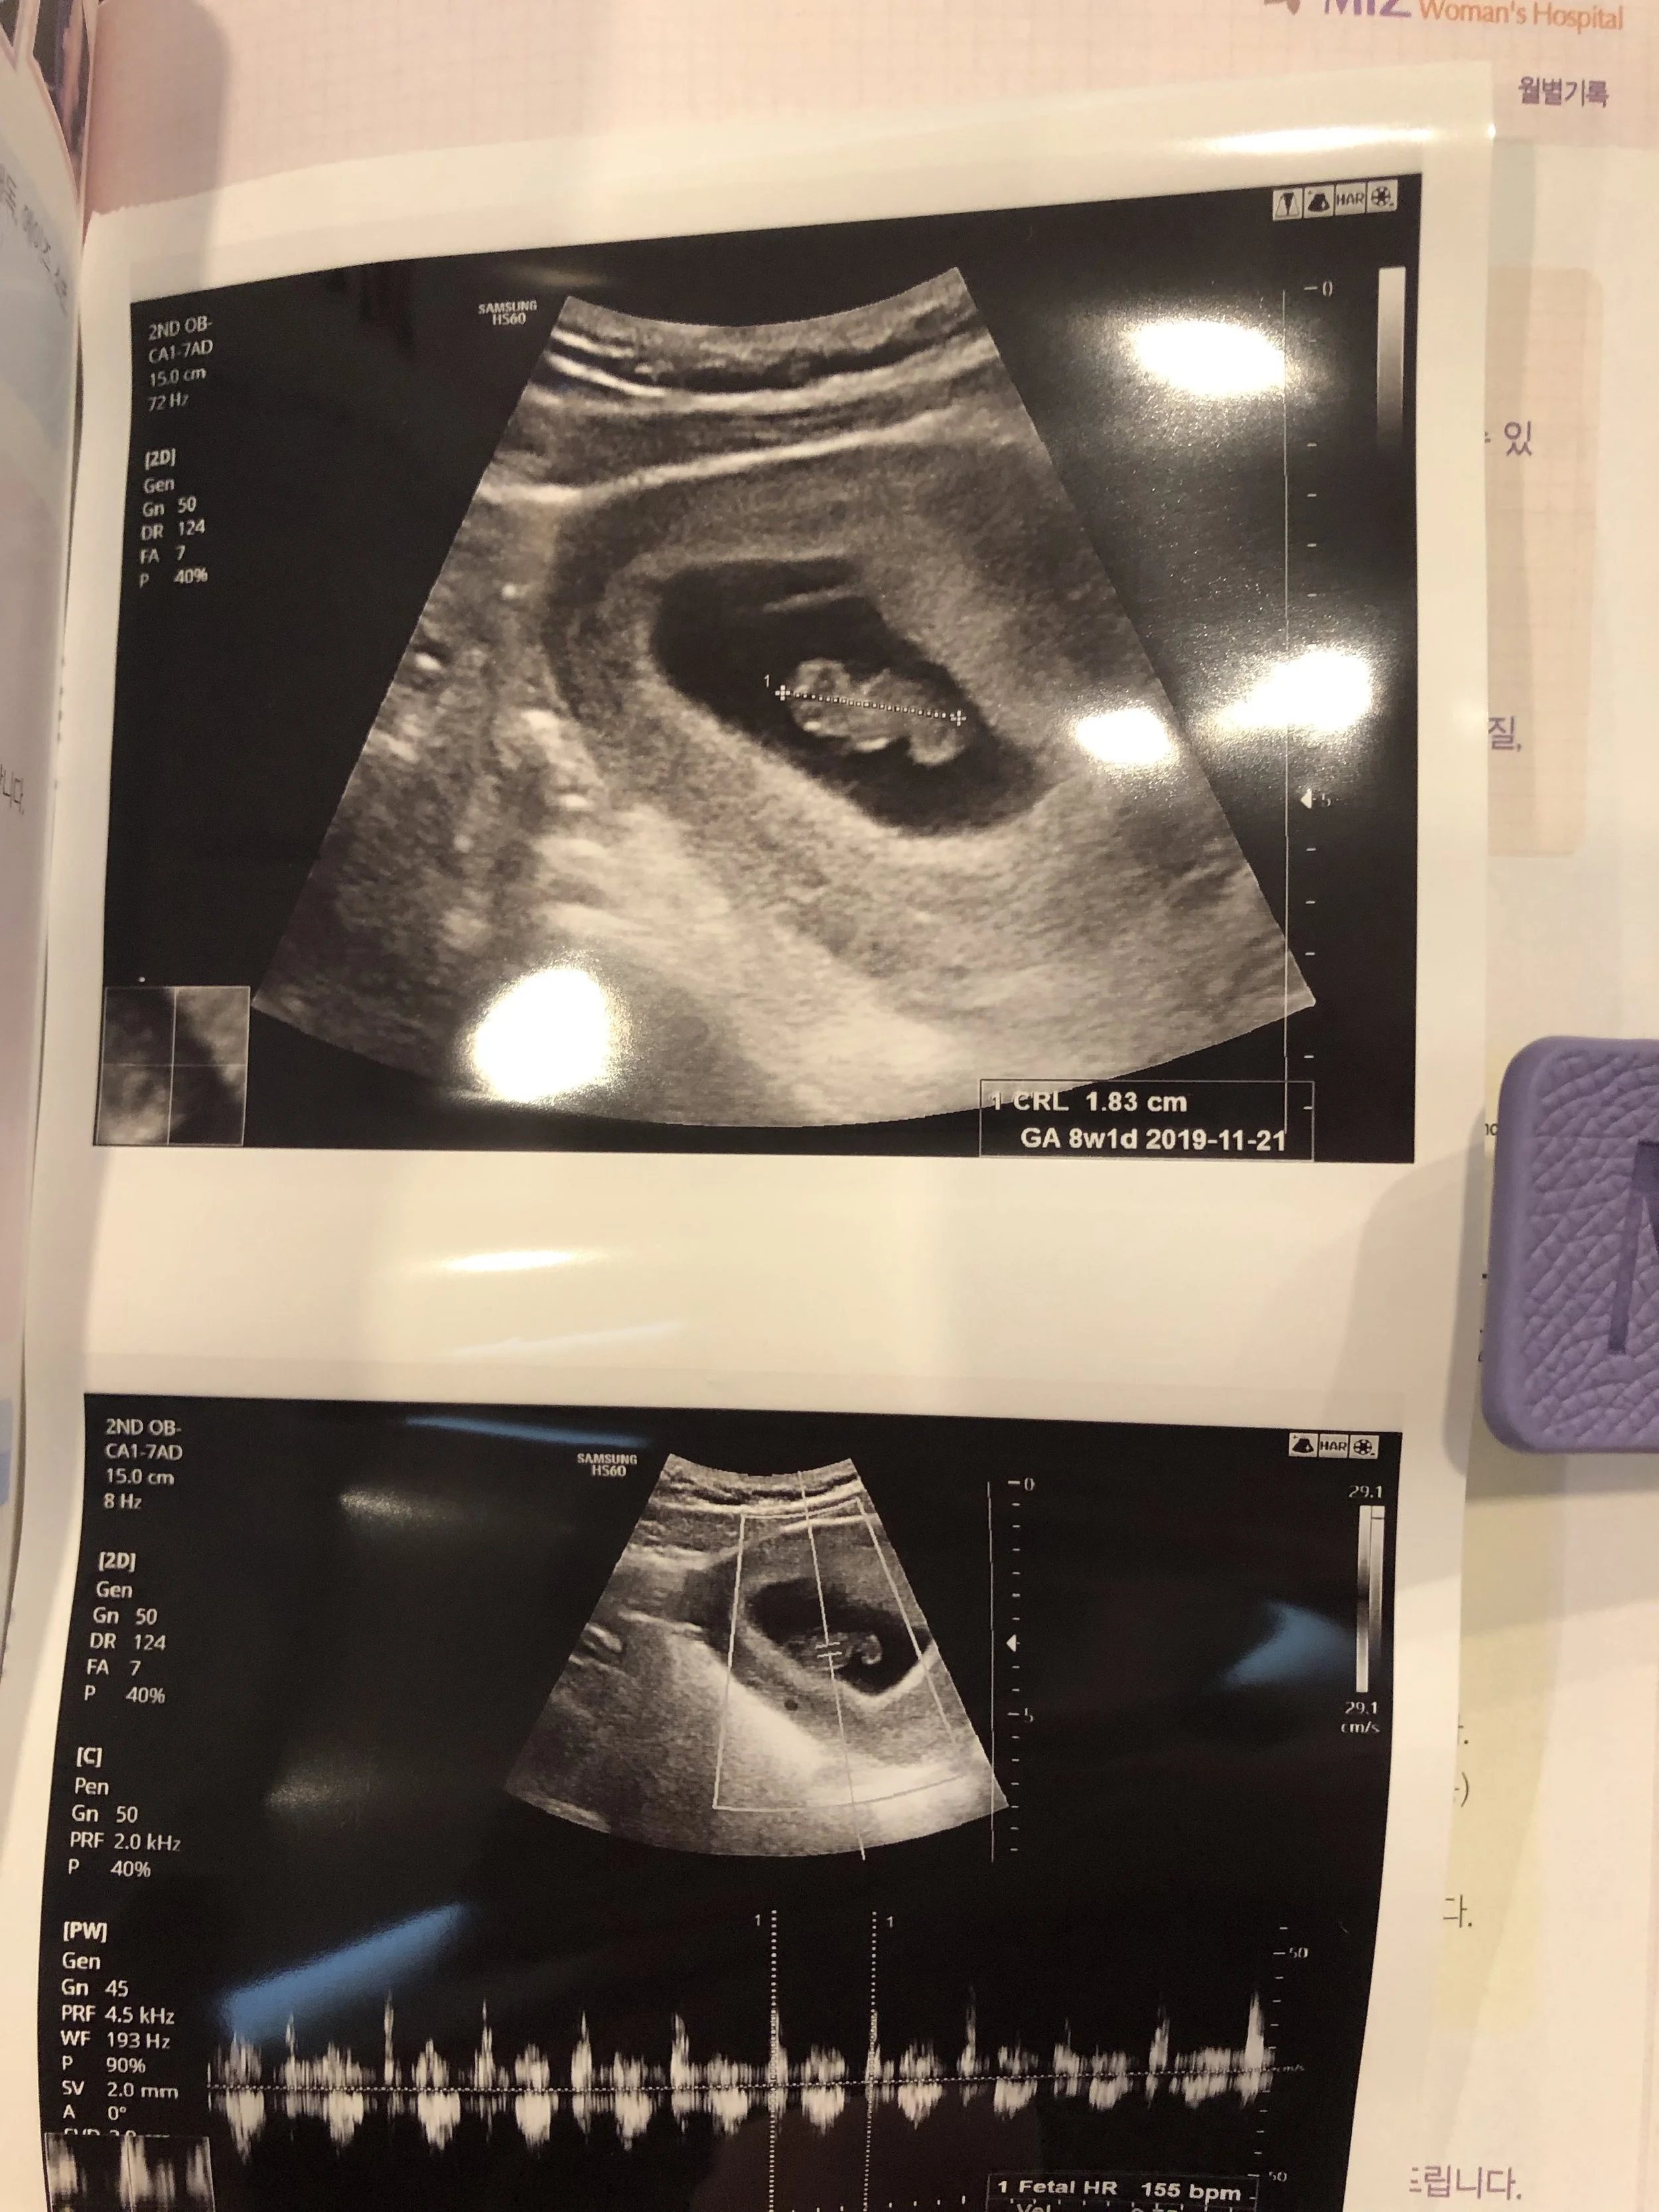

My first ultrasound - we got to hear the heartbeat!

Then I got to eat my favorite pizza and it was a good night. I kept taking pregnancy tests over the course of the next week or so to make sure the lines were getting progressively darker, and we made an appointment at my OB office for a few weeks later, when I would be 8 weeks along. I waited to tell most people until after that appointment so I could have an ultrasound picture.